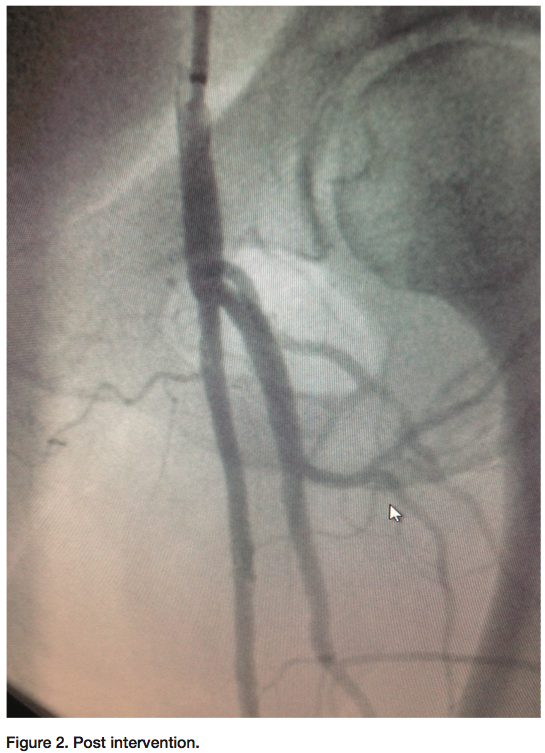

Some of the peripheral cases we perform include chronic total occlusions (CTOs) of the superficial femoral artery (SFA) (Figure 1-2). It may take some time crossing with a wire or crossing device on the proximal cap of the CTO. If trying to cross the CTO cannot be accomplished on the proximal cap of the SFA, gaining access distally may be a better option. Gaining access from a pedal or popliteal artery site is becoming more common. As we perform these interventions, we have access to the distal vessels to manipulate the guidewire up through the CTO from the distal cap first. Crossing the CTO with success from the distal cap works nicely most of the time. We have seen that the distal cap of the occlusion tends to be more crossable than the proximal cap. Once crossed and with verification that the wire is in the lumen of the vessel, the decision is made on what size sheath will be inserted. Depending on whether there are multiple lesions other than the CTO of the SFA, and whether your working access point is going to be from the distal access or from the femoral area, it might require a larger-size sheath. If you choose to work from the femoral area that is probably already accessed from the diagnostic films, then wiring through the lesion and into the sheath that is already across the bifurcation of the iliacs is a good method. Since your wire will be exchange length, grasping the wire tip is easily done. This way, you always have wire access during the entire procedure. The physician’s interventional plans determine the course of action that will be taken. If your interventional plans require you to use a smaller or larger wire (depending on what wire is used to make the initial crossing), the wire can always be exchanged out for a different size. Once the CTO is opened with a balloon, you can always change out the wire using a catheter such as the Seeker Crossing Support catheter (Bard PV) (or the physician’s preferred catheter). This is normally done if the physician decides to use an intravascular ultrasound (IVUS) catheter or any other device that requires the wire to be changed out (Volcano has both an .014 and .038 IVUS catheter).